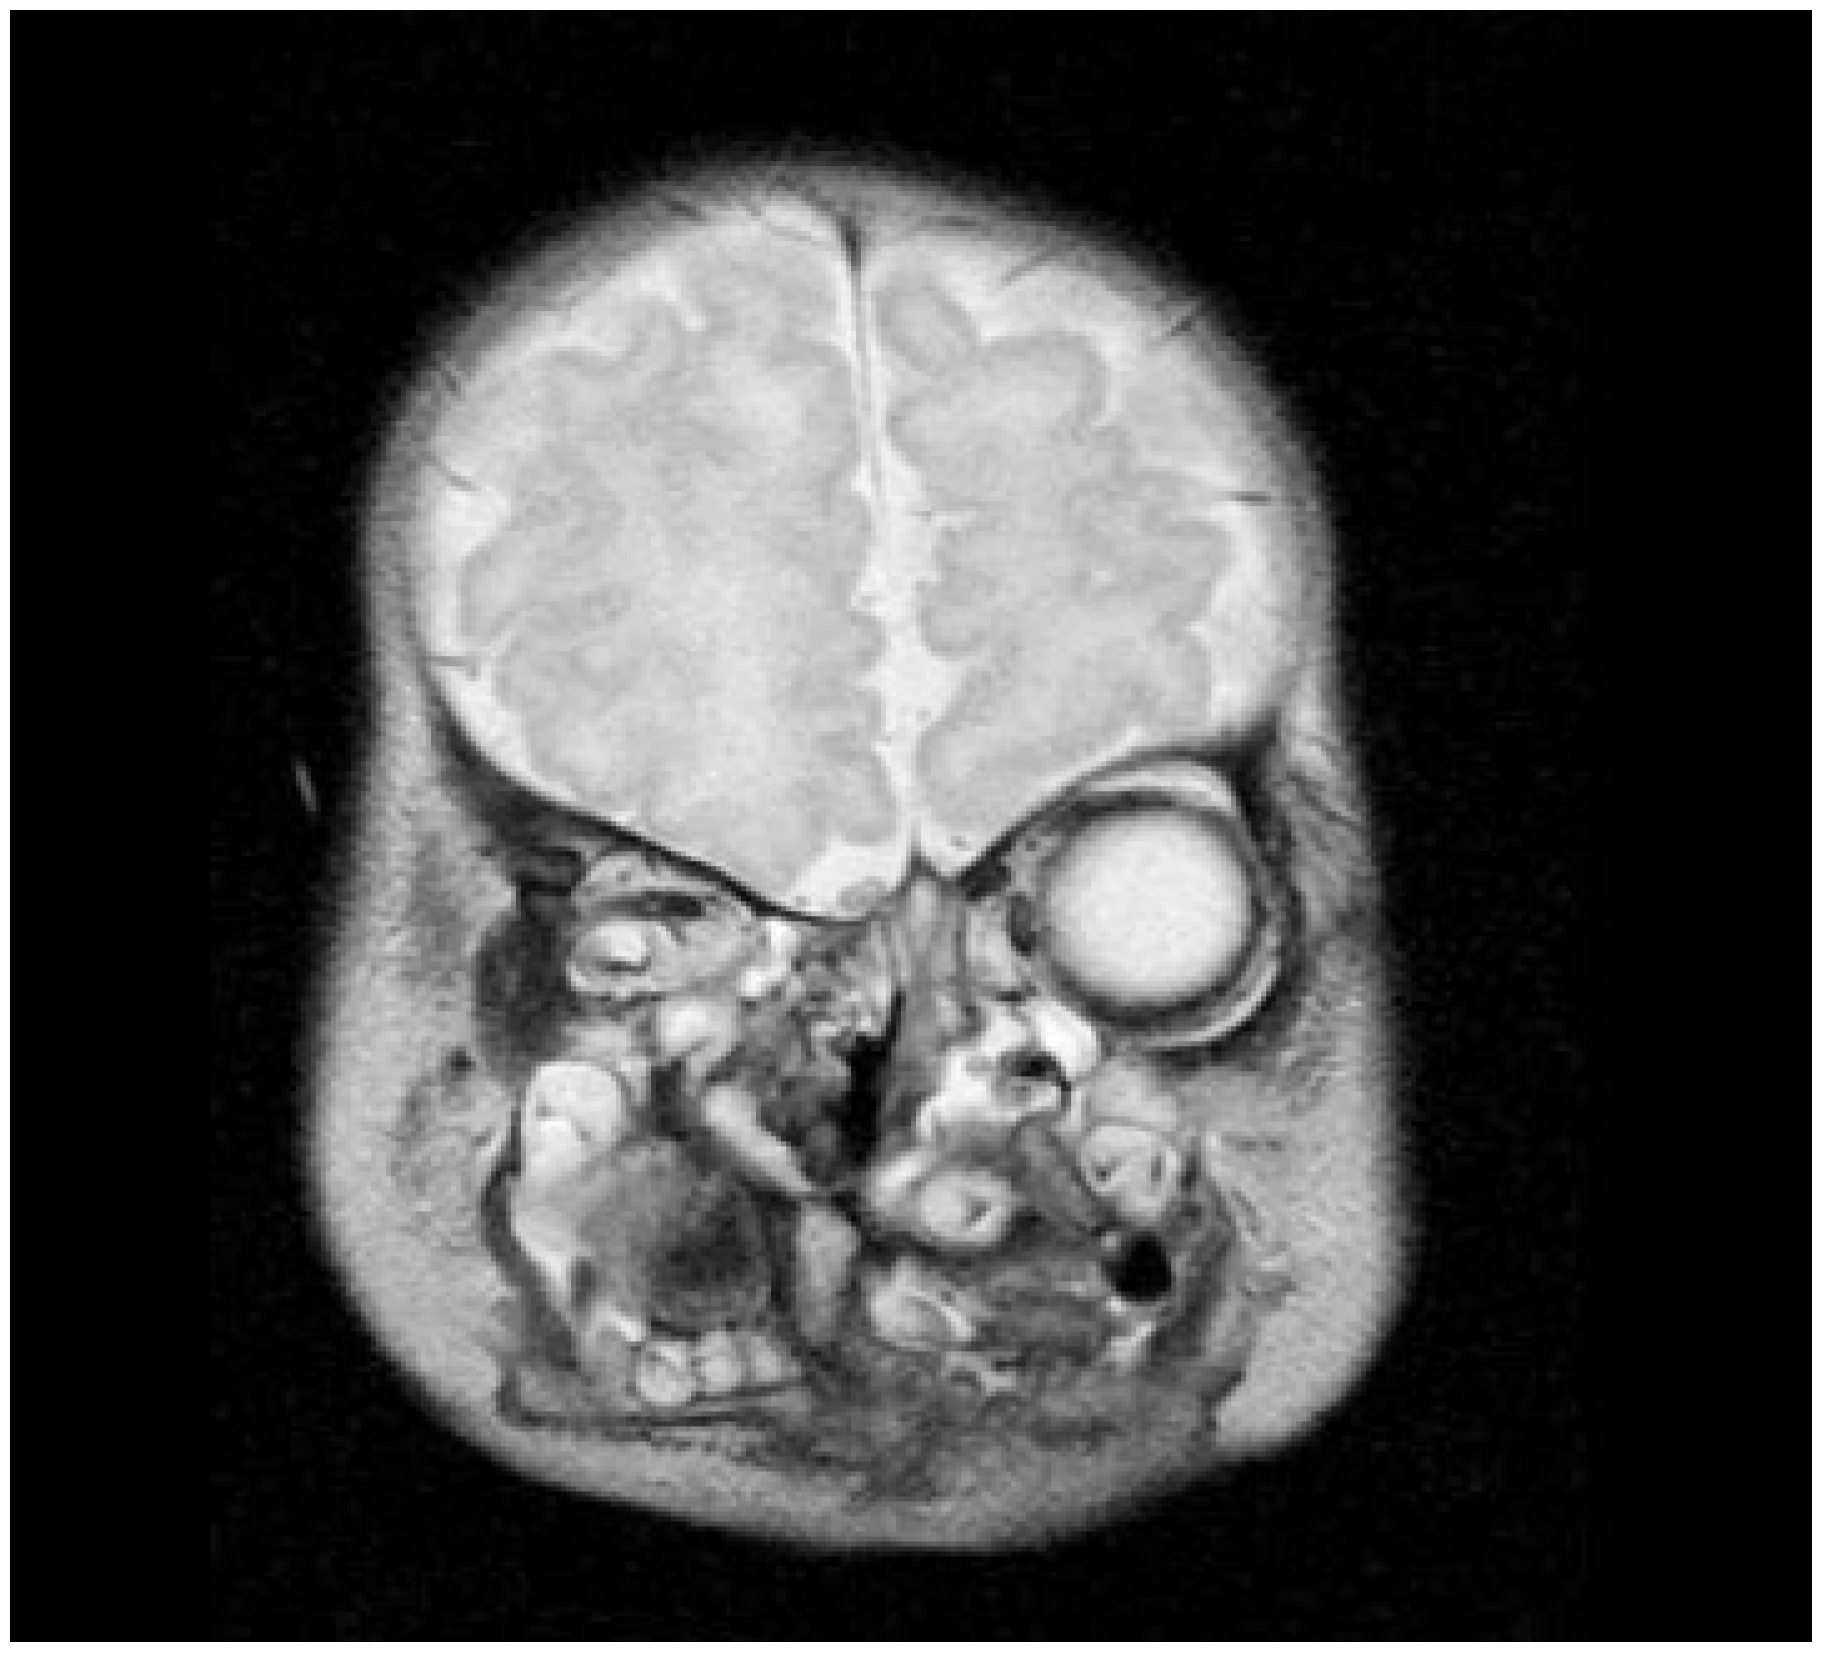

Neonatal examination exhibited frontonasal dysmorphism (bifid anterior cranium, hypertelorism, blepharophimosis, broad nasal bridge, and broad nasal tip), low implantation of the ears, a short neck, bifid and protrusive tongue covered with lanugo, inferior lip and buccolabial sulci malformation, macrostomia, microretrognathia, and except for a small slit in the lateral regions, through which only the end of alveolar ridge could be seen, the mandible and maxilla were fused at gum level (Figure 2). Nasoendoscopy showed complete cleft of the median palate. Magnetic resonance imaging (MRI) revealed orbital hypertelorism, midline cranial cleft ending just superior to the nasal dorsum, agenesis of the corpus callosum, and maxillomandibular fusion (Figure 3 and Figure 4).

Figure 3.

Coronal view on magnetic resonance imaging confirms the midline cranial cleft.